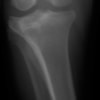

術前左後肢側面像

術前正面像

手術前後のTPA(脛骨高平部の角度)を測定しています。

約29°から約10°へ矯正されています。

本症例は、走った後に左後肢を挙上していることを主訴に来院されました。触診時に左膝関節のクリック音を聴取、レントゲン検査にて左脛骨の前方変位が認められました。術中に、前十字靱帯の断裂及び内側半月板の損傷、内側の軟部組織の顕著な腫脹を確認。半月板切除、TPLOを実施しました。周囲組織への炎症の波及もあったため回復に時間を要しておりますが、徐々に跛行頻度は減少傾向にあり、現在も経過観察中です。術前に約29°あったTPAは術後に約10°まで矯正されました。